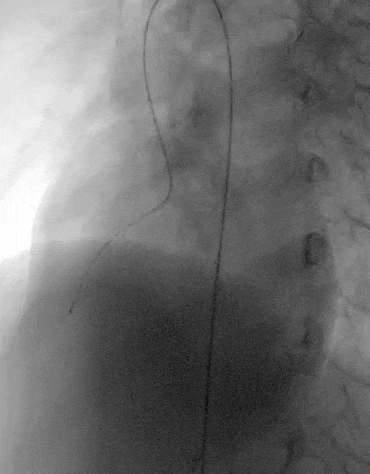

建立输送轨道

飘导丝法导丝过室间隔缺损

圈套器抓捕导丝

送入8F输送鞘

改变输送鞘方向

使输送鞘朝向心尖